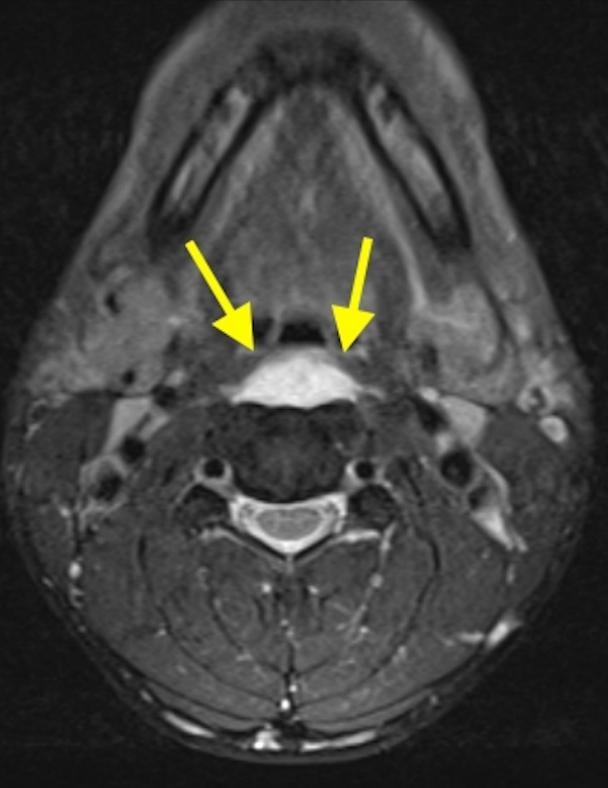

36岁女性,急性颈痛、吞咽困难伴颈部僵硬,MRI示C1-2前部颈长肌增厚呈低信号,提示钙化(长箭头)和C1-4椎前积液(无线箭头),经类固醇和止痛药治疗8天后症状消失,复查MRI提示上述表现消失。(PMID: 18765656)

C1-2前侧低信号(无线箭头)和C1-5椎前水肿(长箭头) (PMID: 19567634)